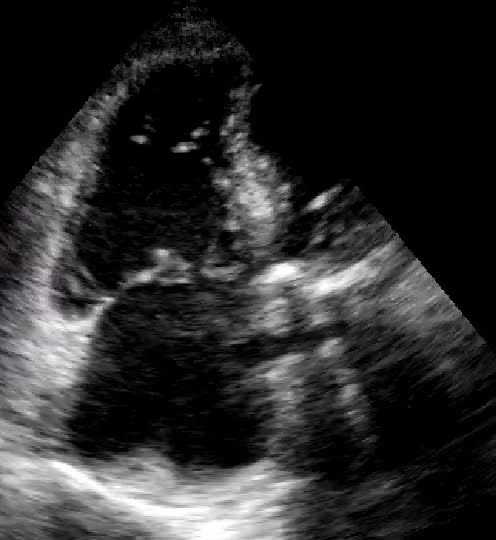

Rete di Chiari

Autore:

Chiara Bencini